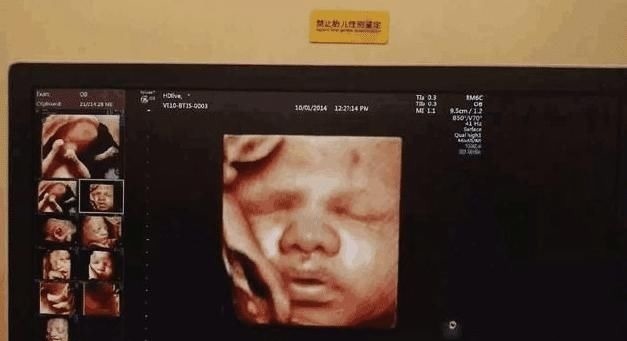

1、本质其实维度不同并不能说明什么,四维只不过是利用技术,让平面的胎儿动起来,让灰暗僵硬的画面变得鲜活,并不能证明胎儿的发育情况,只是让孕妈提前心里有个数,直到自己的宝宝大概长什么样子而已。知道了这个检查的本质,很多孕妈是不是觉得四维彩超也不是非做不可呢?【 四维彩超|怀孕之后,孕妈做四维前要清楚的3件事,不然可能会白白浪费钱】

2、时段不管是什么仪器,既然能够穿透孕妈的肚皮,探知到孕妈肚皮深处的秘密,那必然是有着辐射的,如果孕妈总是频繁的做这种检查,那么肚子里的宝宝也会多次接触到有辐射的仪器,这对宝宝的生长发育肯定是有害的。而且孕妈想要做四维彩超,最佳的时间是等胎儿孕育满20个周以后再去检查,因为这个时候胎儿已经初步成型,这个时候做检查孕妈就可以大概的看出自己的宝宝模样如何,如果检查过早,孕妈什么结果都看不到,还要白白浪费很多钱。孕妈在怀孕期间,想要了解宝宝的发育情况,也可以准备一个胎心监测仪,可以快速清晰反馈胎儿心跳,连接了手机智能录音功能,可以记录胎儿心跳,更可安抚胎儿情绪。

3、效果至于四维彩超能不能检查出什么,这还要看医生的水平,如果是一个经验丰富的老医师来帮孕妈检查,那么她一定能从四维的动图观察出胎儿的一些缺陷来,但是那些还没有见过很多案例的年轻医师很有可能就发现不出宝宝的异样了。因此,四维也并不是非做不可,做了最多也只能满足孕妈心中的一个念想,其实并不能精准的看出宝宝的发育状况如何。在孕晚期,孕妈的睡眠是很重要的,但是因为肚子已经很大,这就会让很多孕妈出现失眠的情况,这时不仅孕妈不仅需要找到一个舒适的睡姿,还需要用侧睡枕来辅助睡眠,孕妈有必要给自己准备一个,更好地保护宝宝。